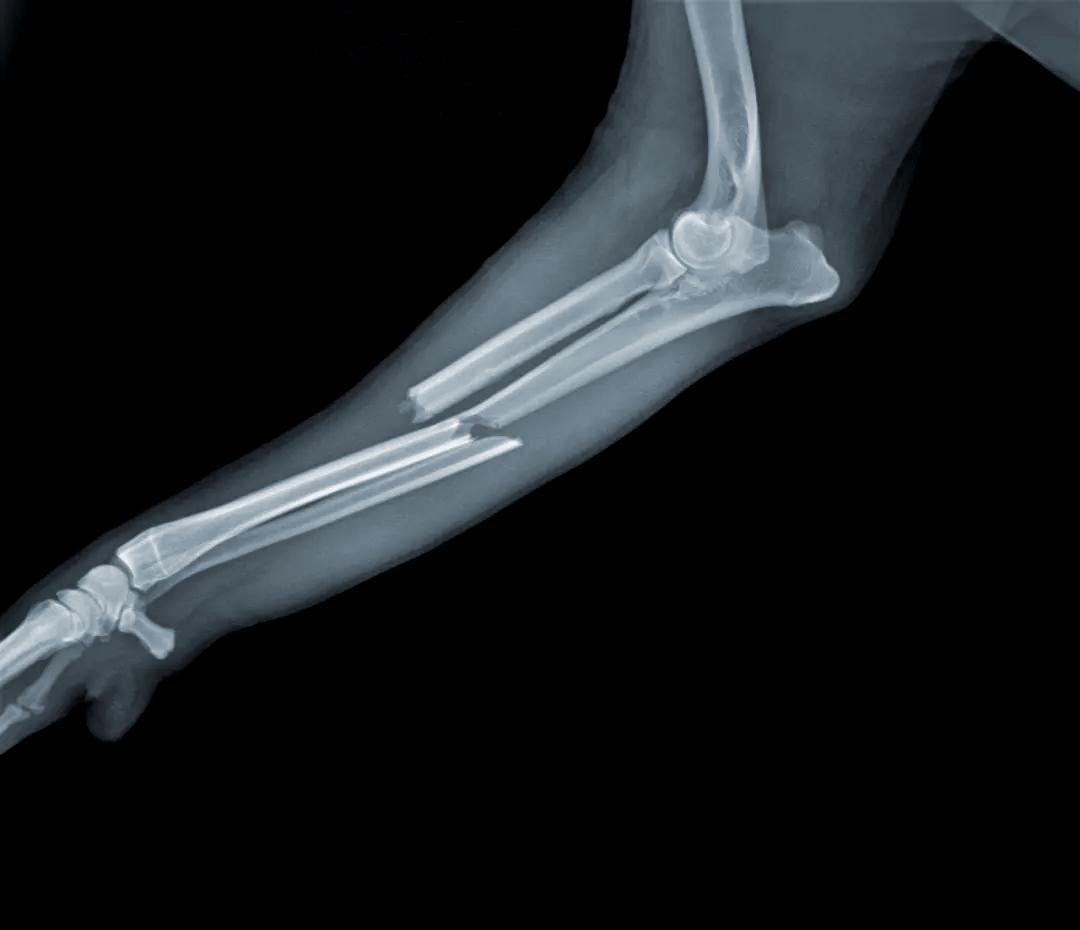

其次因爲血壓降低、血脂和血糖代謝速度減緩,骨骼無法獲取足夠的能量,會出現骨密度比一般人更低的情況,也就是骨質疏鬆

沒有強壯的骨骼支撐,身體出現骨折的可能性也會大幅度提升。

(古代太監更容易骨折)